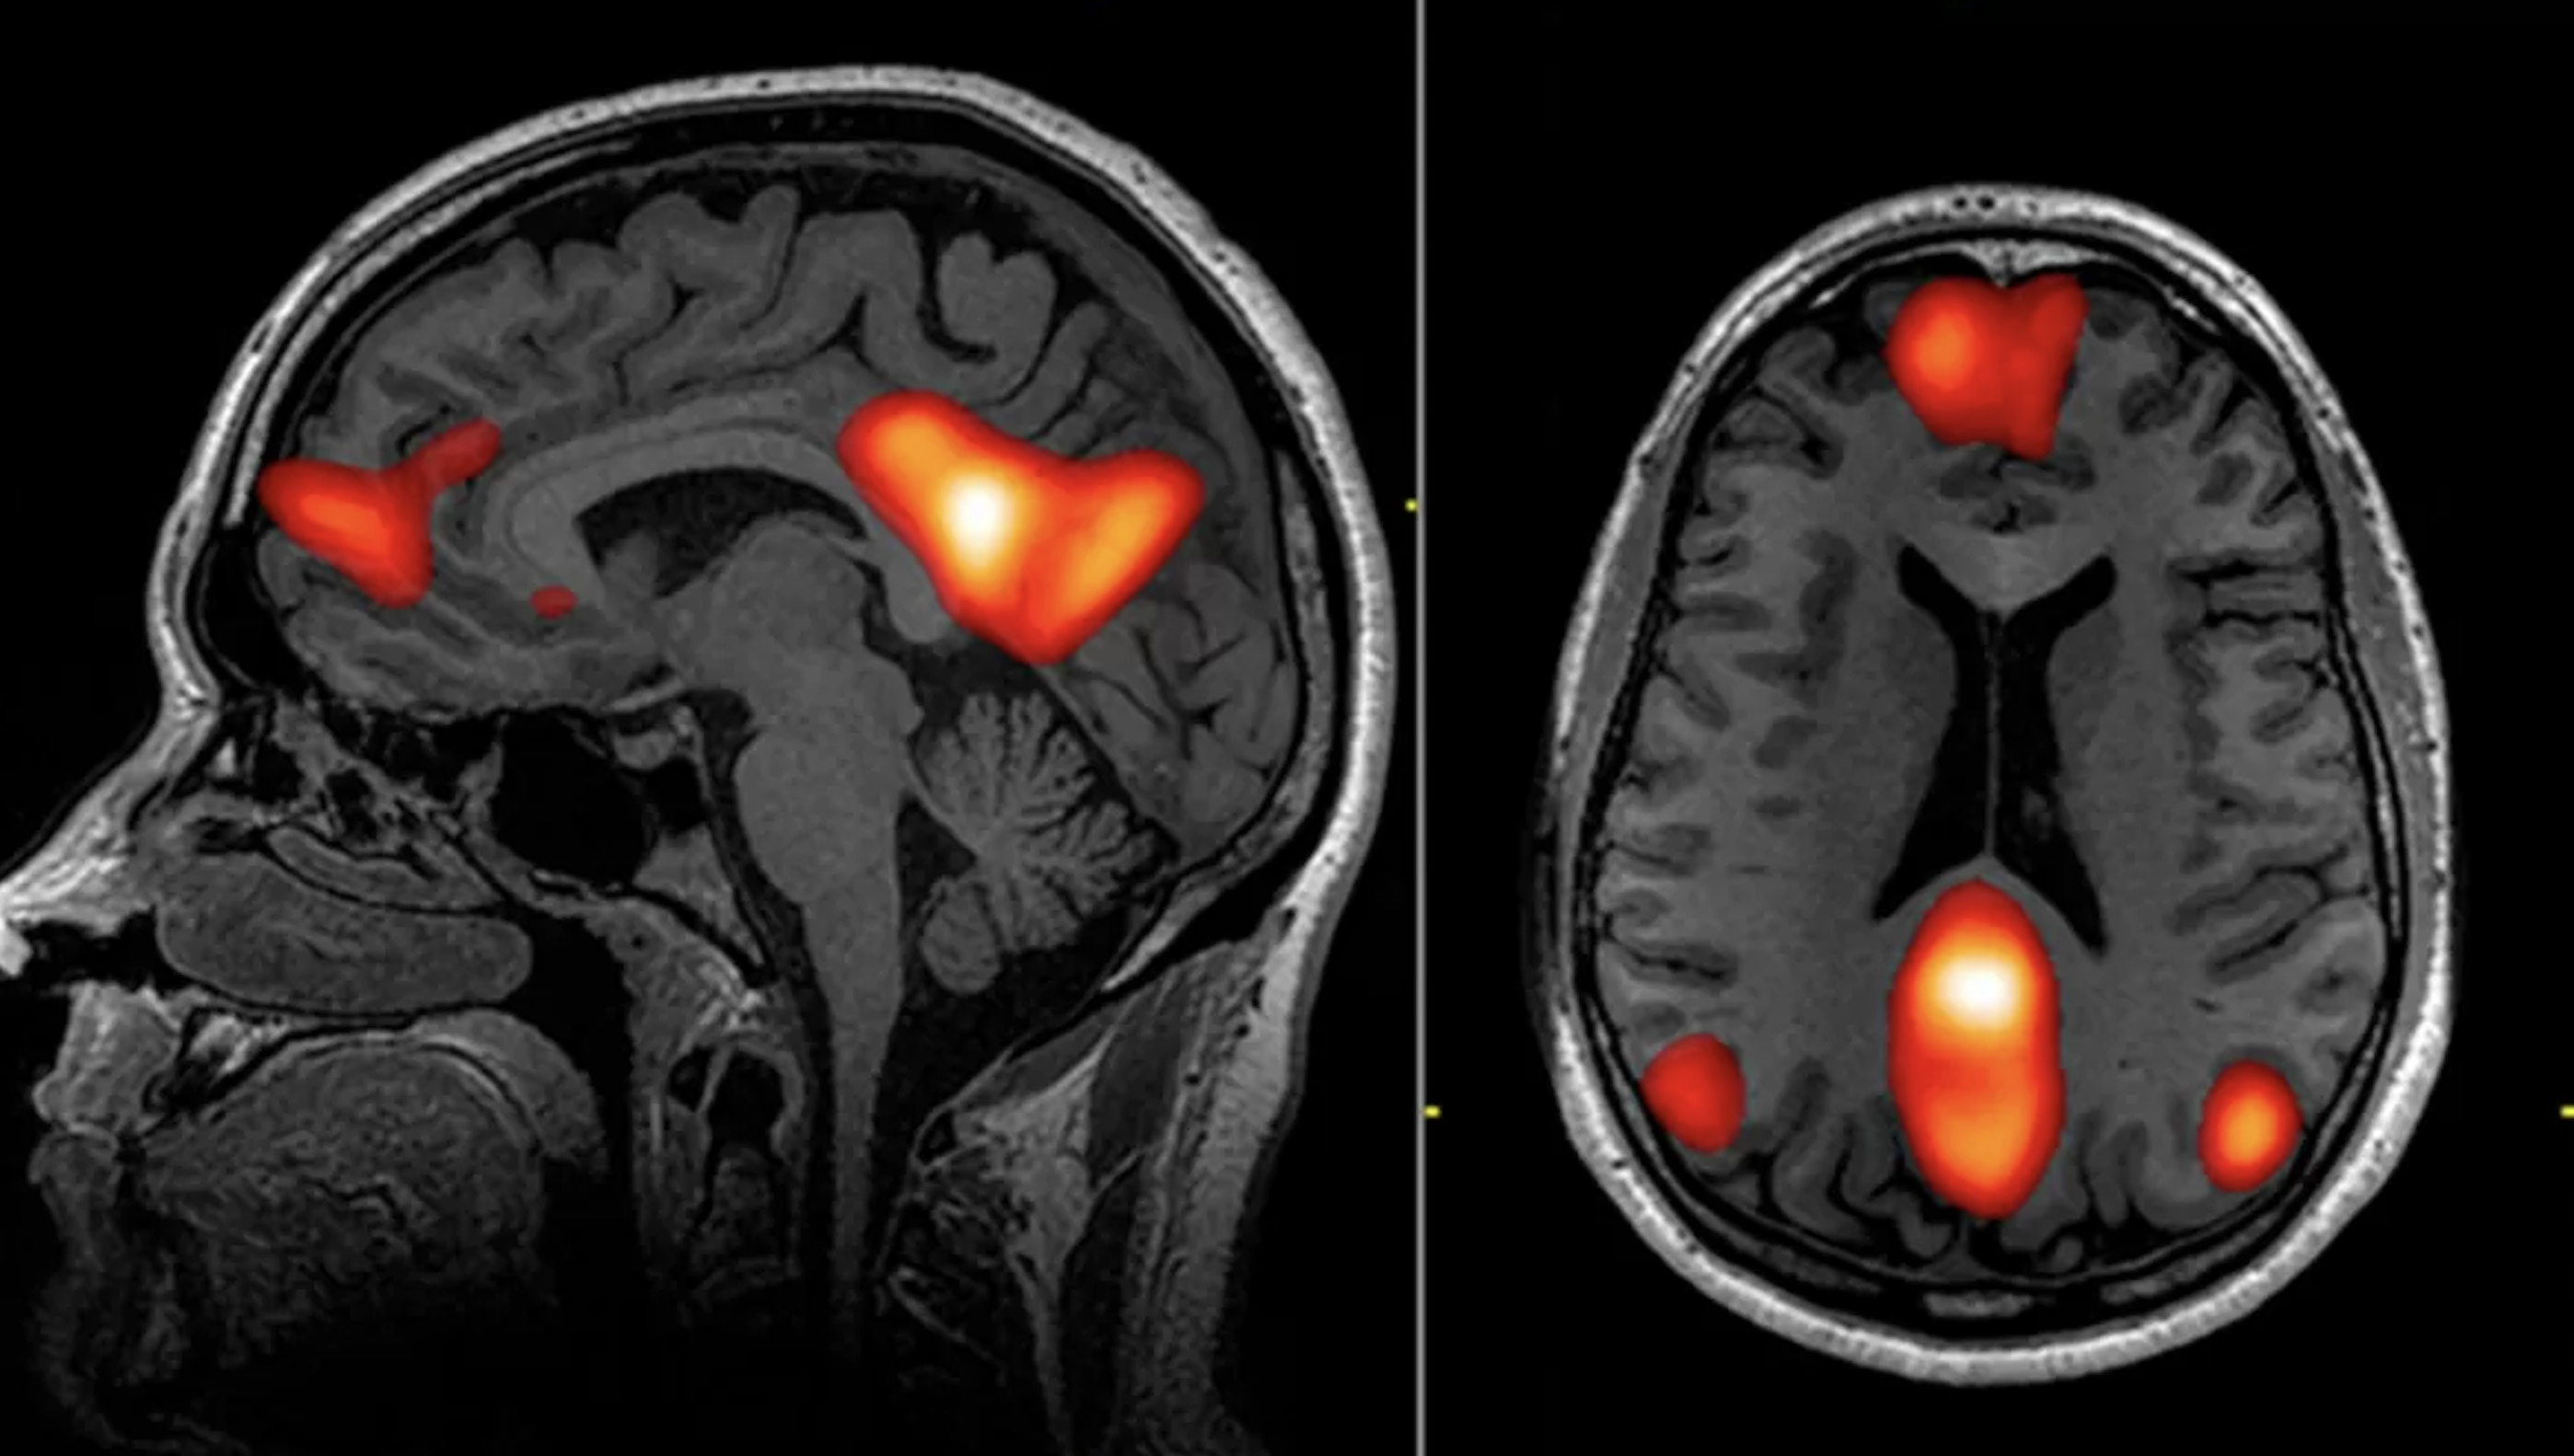

Default Mode Network (DMN), czyli tzw. sieć stanu domyślnego, to jedno z najbardziej intrygujących odkryć współczesnej neurologii. To zespół połączeń neuronowych, który aktywuje się, gdy człowiek nie wykonuje żadnego konkretnego zadania zewnętrznego – czyli w stanie spoczynku umysłowym. Zamiast wyciszenia, mózg wówczas wcale nie przestaje pracować – wręcz przeciwnie, intensywnie zajmuje się analizowaniem, planowaniem, przypominaniem sobie wydarzeń z przeszłości oraz konstruowaniem narracji o samym sobie.

DMN obejmuje kilka kluczowych obszarów mózgu, w tym przyśrodkową korę przedczołową, tylną część zakrętu obręczy oraz okolice kory ciemieniowej. To w tej sieci zachodzą procesy autorefleksji, myślenia o sobie, analizowania relacji społecznych oraz snucia fantazji i symulacji przyszłości. Choć ta funkcja jest niezbędna dla budowania spójnego obrazu siebie i orientacji w świecie społecznym, to jej nadaktywność może prowadzić do patologicznego zamknięcia się w myślach, nadmiernej ruminacji, stanów depresyjnych i lękowych. Ciekawym zjawiskiem jest fakt, że aktywność DMN ulega istotnemu osłabieniu w określonych warunkach, co prowadzi do zmniejszenia poczucia „ja” i osłabienia granic ego. Takie zjawisko obserwuje się m.in. podczas medytacji, w stanie głębokiego skupienia (flow), a także w wyniku stosowania niektórych substancji psychodelicznych, takich jak psylocybina (z grzybów halucynogennych), LSD, DMT czy ketamina.

W badaniach z użyciem funkcjonalnego rezonansu magnetycznego (fMRI) wykazano, że pod wpływem psylocybiny aktywność DMN znacząco spada.